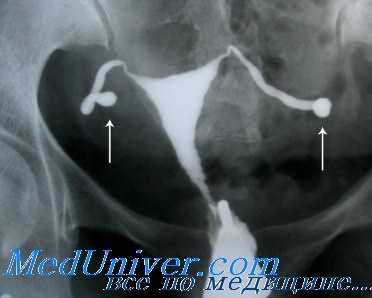

Серологические исследования на хламидии также могут сыграть свою роль при обследовании бесплодной пары. К примеру, если результаты первичного обследования, включающего ГСГ, оказались в пределах нормы, традиционно следующим шагом становится лапароскопия. Однако остается неясным, стоит ли применять лапароскопию в том случае, если у пациентки не было ЗППП или хронических болей, так как нет точной уверенности, что вероятность обнаружения какого-либо заболевания перевесит риск самой процедуры. В такой ситуации принять решение поможет анализ на антитела к хламидиям.

Проба на антитела к хламидиям — серологическая реакция, определяющая титр антихламидийных антител, состоящих из иммуноглобулина G. Эффективность этой реакции в определении вероятности поражения фаллопиевых труб хламидиями изучали в течение многих лет. Соображения о чувствительности этого метода основаны на следующем. Во-первых, серологическое исследование не дает возможности отличить существующую хламидийную инфекцию нижней части полового тракта от существующего либо перенесенного поражения трубы. Также, по некоторым оценкам, существует перекрестная реактивность между Chlamydia pneumoniae и полисахаридами грамотрицательных бактерий.

Метаанализ 23 исследований с общим количеством 2729 пациенток, прошедших лапароскопию и тест на антихламидийные антитела сыворотки крови, показал, что проба с энзимосвязанным иммуносорбентом и реакция иммунофлюоресценции оказались самыми точными в диагностике какой-либо трубной патологии: они могут быть сравнимы с гистеросальпингографией (ГСГ).

Подытоживая, можно сказать, что проба на антитела к хламидиям имеет свои ограничения, но оказывается полезным инструментом для скрининга применительно к определенной подгруппе (бесплодные женщины), помогая выделить из них тех, кому потребуются инвазивные методы обследования.

Некоторые специалисты в области лечения бесплодия предложили методику изучения патологии маточных труб, начинающуюся с серологического анализа на хламидии. Если результат отрицательный, считают они, то в дальнейшей ГСГ нет необходимости. Если же серьезные подозрения вызывает наличие в анамнезе пациентки перенесенных инфекционных заболеваний или серологический анализ дал значительные показатели, для дальнейшего исследования можно применить ГСГ или лапароскопию. Последний метод позволит получить патогенные микроорганизмы из маточных труб или Дагласова кармана.